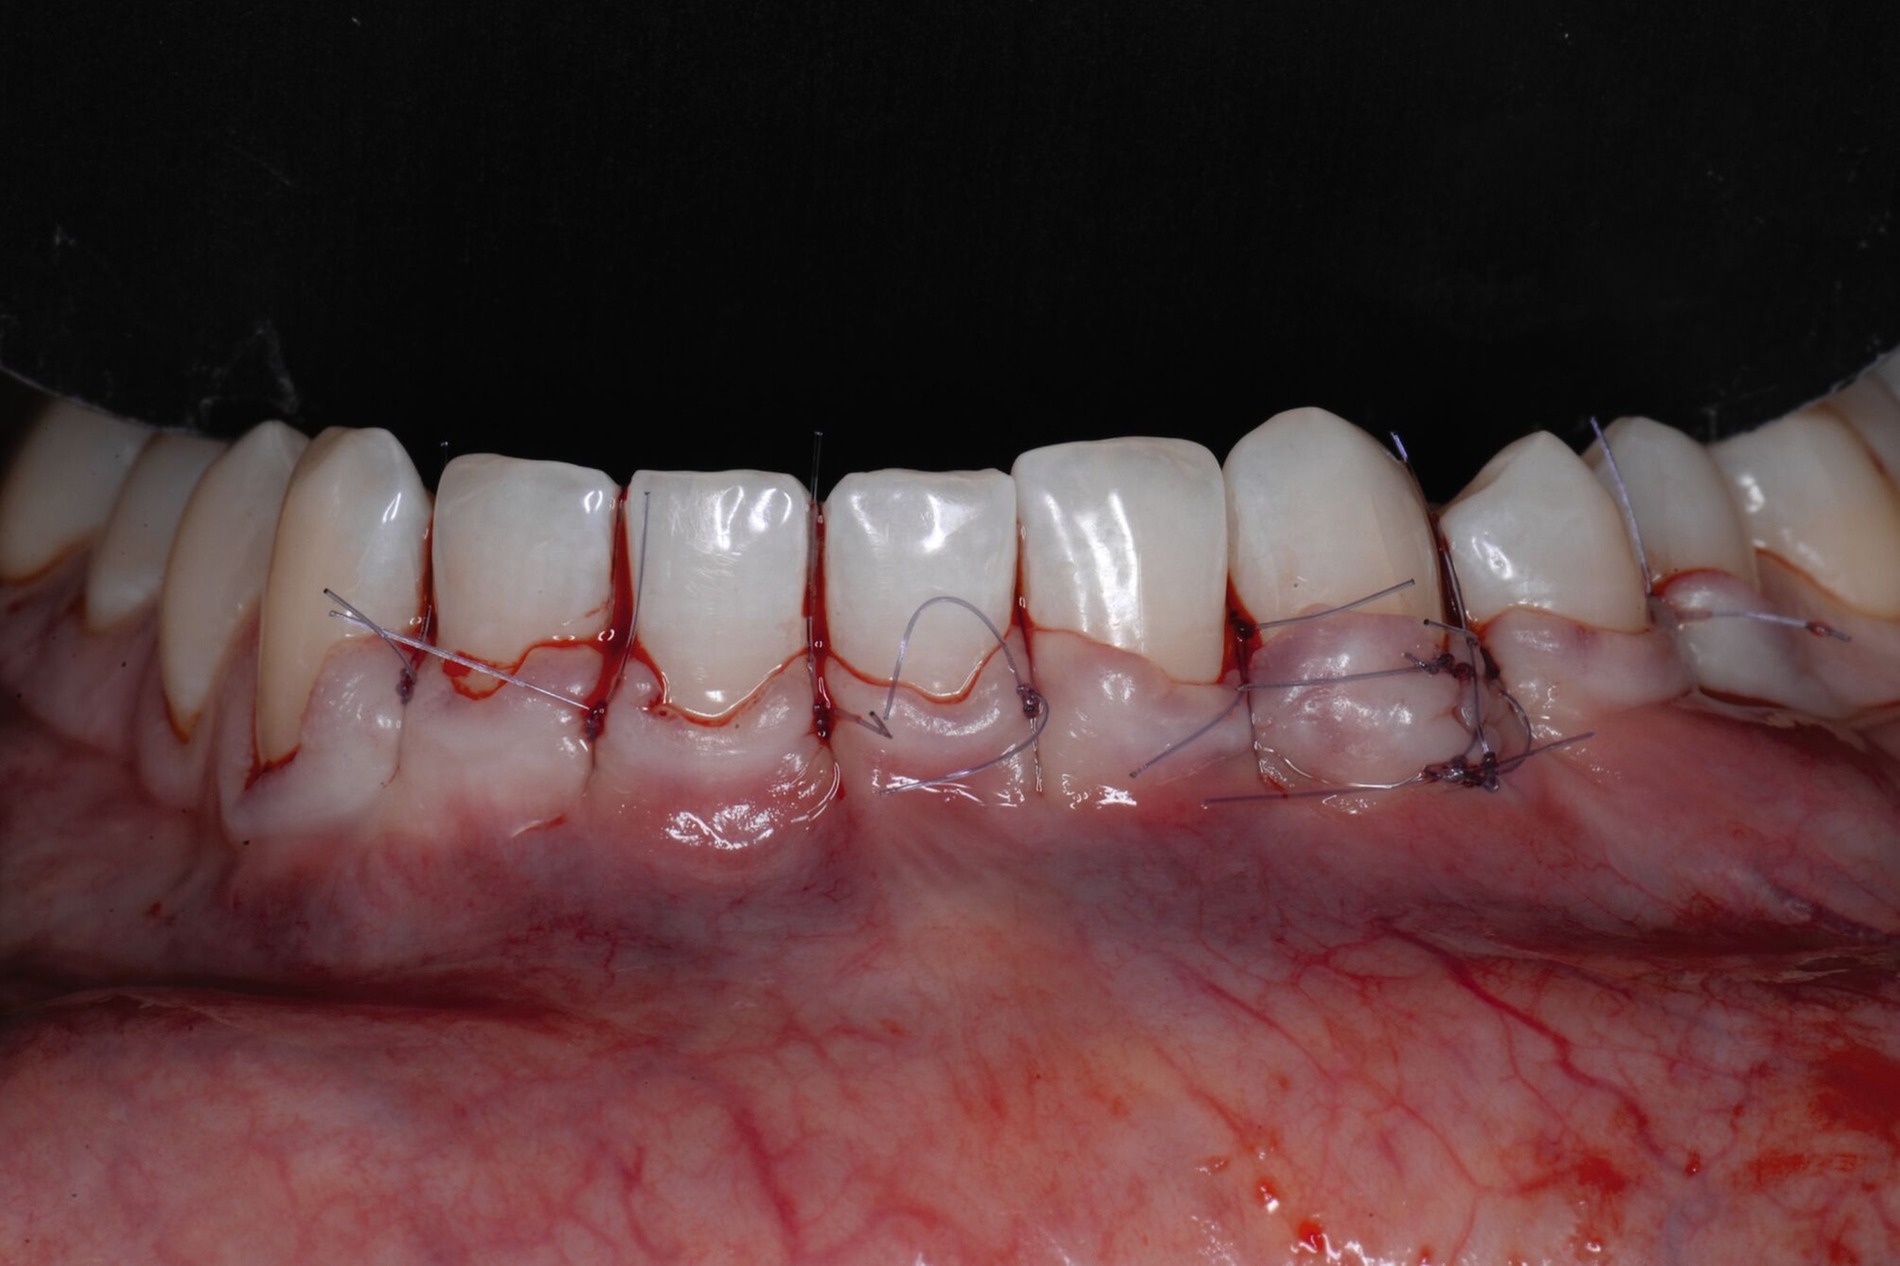

Tunkel et al. versuchten die Vorteile von Zucchellis Koronalem Verschiebelappen und Sculeans Lateral Geschlossenem Tunnel in einer Technik zu vereinen: dem Lateral Geschlossenen Koronalen Verschiebelappen (LCAF) [Tunkel et al., 2024] (Abbildung 3). Bei dieser Methode, mit der vor allem tiefe singuläre parodontale Rezessionen behandelt werden, wird die Koronalverschiebung ohne Entlastungsinzisionen kombiniert mit dem lateralen Verschluss der tiefen parodontalen Rezession.

Das Vorgehen ist hier wie folgt: Zunächst wird im Bereich der tiefen Rezession der Gingivarand geringfügig exzidiert, um ein Zusammenwachsen der geschlossenen Lappenanteile zu ermöglichen. Anschließend wird der Schnitt in horizontaler Richtung durch leicht bogenförmige Schnittführungen auf Höhe der Schmelz-Zement-Grenze erweitert, um mindestens zwei Zähne rechts und links von der Rezession (Abbildung 3b). Im Unterkiefer-Frontzahnbereich, wo die Rezessionen heutzutage am häufigsten vorkommen, sollte der Lappen mindestens von Eckzahn zu Eckzahn gebildet werden, um ein harmonisches Ergebnis nach Abheilung zu erreichen. Auf vertikale Entlastungsinzisionen kann komplett verzichtet werden. Anschließend erfolgt die Lappenpräparation nach dem bereits für koronale Verschiebelappen gängigen Prinzip teilschichtig-vollschichtig-teilschichtig.

Die Papillenbereiche werden mit dem Skalpell scharf vom Periost abgelöst. Dann wird das Periost durchtrennt und bis zur mukogingivalen Grenze ein vollschichtiger Lappen gebildet. Nach Überschreiten dieser wird wieder zweischichtig präpariert. Hierdurch wird eine gute Mobilisation des Lappens erreicht, die eine ausreichende Koronalverschiebung ermöglicht. Entgegen dem in früheren Jahren propagierten komplett teilschichtigen Vorgehen, kann durch dieses Verfahren die Gefahr von Lappenperforationen signifikant gesenkt werden, da diese insbesondere im Bereich der mukogingivalen Grenze auftreten. Nachdem die Lappenareale mesial und distal der Rezession gelöst sind, können diese durch zwei bis drei feine monofile Nähte miteinander verbunden werden (Abbildung 3c). Sobald durch diese Naht ein zusammenhängender koronaler Verschiebelappen entstanden ist, werden die Papillenbereiche koronal des gebildeten Lappens entepithelialisiert. Nach Entnahme eines Bindegewebstransplantats oder entepithelialisierten freien Schleimhauttransplantats wird die Wurzeloberfläche mit EDTA-Gel konditioniert und anschließend werden Schmelz-Matrix-Proteine aufgetragen (Abbildung 3d). Diese bewirken die Bildung eines new attachment und fördern zudem die Wundheilung, was gerade bei den delikaten lateralen Verschiebelappen von Vorteil sein sollte [McGuire und Cochran, 2003; Almqvist et al., 2011; Thoma et al., 2011; McGuire et al., 2016]. Anschließend wird das Transplantat durch Nähte ausgehend vom oralen Papillenbereich fixiert (Abbildung 3e). Zuletzt wird der Lappen mit sogenannten doppelten Umschlingungsnähten im Bereich der Papille durch Zug nach koronal und oral fixiert, was eine perfekte Positionierung ermöglicht [Zuhr et al., 2009] (Abbildung 3f). Hierbei muss darauf geachtet werden, dass der Lappen die Schmelz-Zement-Grenze um mindestens 2 mm überdeckt, um eine hundertprozentige Wurzeldeckung erwartbar zu machen [Pini Prato et al., 2005].

Der Lateral Geschlossene Koronal Verschobene Lappen ermöglicht eine annähernd narbenfreie Deckung singulärer parodontaler Rezessionen durch Verzicht auf vertikale Entlastungsinzisionen (Abbildung 3g). Das Lösen der Papillen im Rahmen der Verschiebung ermöglicht eine deutliche Anhebung des Lappens und somit durch großzügige Überdeckung das Erreichen vollständiger Wurzeldeckungen. Durch den lateralen Verschluss im Rahmen der tiefen, über die mukogingivale Grenze hinausgehenden Rezession kann keratinisierte Gingiva im Bereich dieser hergestellt und eine übermäßige Mobilisation und damit Einschränkung des Vestibulums verhindert werden.